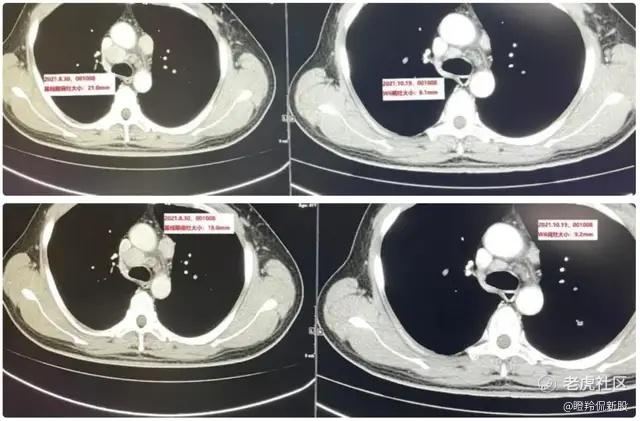

维贝柯妥塔单抗的“缩瘤”能力非常强,基于独特的“生物导弹”设计(高亲和力抗体、可裂解Linker和强效Payload杀伤),维贝柯妥塔单抗的疗效已在后线鼻咽癌和头颈鳞癌得到验证:以一位治疗线数为4的转移晚期鼻咽癌患者为例,仅入组维贝柯妥塔单抗的II期临床试验并接受维贝柯妥塔单抗治疗仅2次(6周),靶病灶直径总和缩小53.1%,疗效评估PR。

(左为治疗前,右为治疗后)